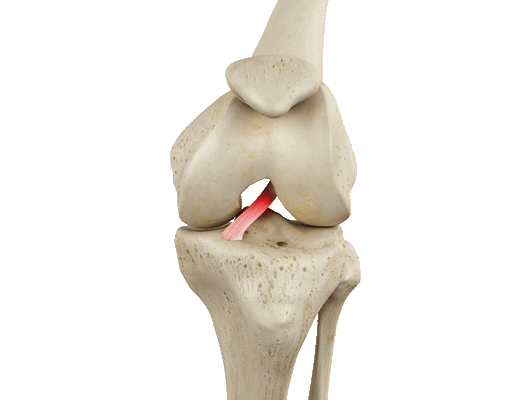

Передняя крестообразная связка (лат. lig. cruciatum anterius) начинается от задневерхней части внутренней поверхности наружного мыщелка (костного выступа) бедренной кости, пересекает полость коленного сустава и прикрепляется к передней части передней межмыщелковой ямки большеберцовой кости также в полости сустава. Крестообразная связка стабилизирует коленный сустав и не дает голени чрезмерно смещаться вперед, а также удерживает наружный мыщелок большеберцовой кости. Задняя крестообразная связка коленного сустава (лат. lig. cruciatum posterius) начинается от передневерхней части боковой поверхности внутреннего мыщелка бедра, пересекает коленный сустав и прикрепляется к задней межмыщелковой ямке большеберцовой кости. Она стабилизирует коленный сустав, и удерживает голень от смещения назад.

Суставные поверхности костей покрыты хрящом. Между сочленяющимися поверхностями бедренной и большеберцовой костей имеются внутренний и наружный мениски, представляющие собой серповидные хрящи. Коленный сустав заключен в суставную сумку. У человека коленное сочленение допускает движения сгибания и разгибания, а при согнутом положении — и вращение вокруг оси.

Передняя крестообразная связка отвечает за динамическую устойчивость коленного сустава, фиксируя голень от нефизиологического смещения кпереди и поддерживая наружный мыщелок большой берцовой кости. Более 1/2 стабильности коленного отдела обеспечивается благодаря ПКС. Именно поэтому данную структуру специалисты называют первым стабилизатором колена, без нее сустав нормально работать не сможет. Располагается она в самом центре костного соединения, перекрещиваясь с задней крестообразной связкой х-образно, что и дало этим двум структурным элементам одноименные названия. Мы же будем говорить сейчас конкретно о ПКС и посттравматической реконструктивно-пластической ее коррекции.